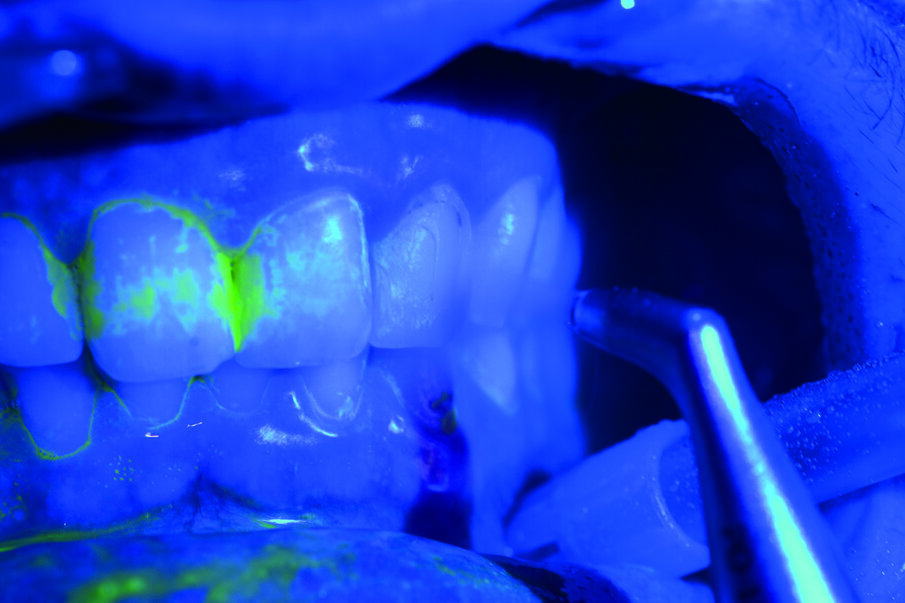

Prima del trattamento abbiamo applicato un rilevatore di placca alla fluoresceina Plac-o-Tect (Directa) per evidenziare la topografia della presenza di biofilm batterico nel cavo orale. Osserviamo la topografia del biofilm batterico presente e condividiamo con il paziente i siti più ritentivi di biofilm batterico in modo da avere una comunicazione non verbale del rivelatore, utile per il rinforzo motivazionale del paziente con l’obiettivo di migliorare l’efficacia dell’igiene orale domiciliare (Fig. 3).